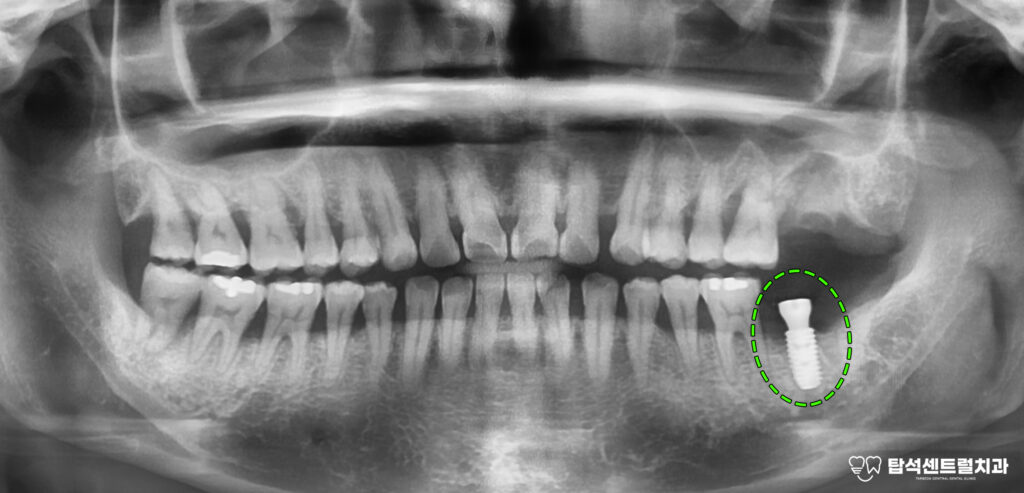

엑스레이 촬영을 통해 구강 상태를

확인하면 치주염으로 인한 전반적인

치조골 소실이 관찰되는 경우가 적지 않습니다.

치조골은 이를 지탱하는 뼈 조직으로

이 부분이 손상되면

치아 동요도가 증가하게 됩니다.

27번과 37번처럼

심한 동요도와 함께

통증을 호소하는 상황에서는

발치를 고려해야 되는 단계에

이르게 됩니다.

반면 아래턱 치아는 발치 즉시 식립이

가능한데, 이는 치조골 상태가 비교적

양호하고 초기 고정력을 확보할 수 있기 때문입니다.

아랫니 부위에 즉시 임플란트 식립과

발치와 보존술을 진행하기로 합니다.

당일 아랫니는 발거 후

픽스처를 심는 방식으로 진행됩니다.

즉시 식립은 발치와 식립을 한 번에 해결하여

치료 기간을 단축시킬 수 있다는 특징이 있습니다.

다만 뼈의 상태가 충분히 건강해야 하고

초기 안정성을 확보할 수 있어야 가능합니다.